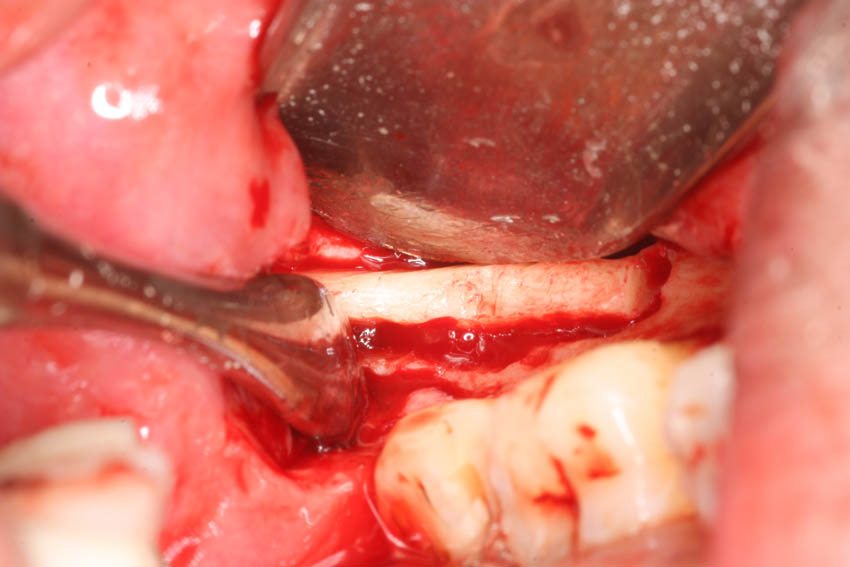

→ Ανύψωση του εδάφους του ιγμορείου με τη μέθοδο του οστικού παραθύρου.

→ Λήψη μοσχεύματος αυτογενούς οστικού μπλοκ από τον κλάδο.

→ Τεχνική διχασμού της φατνιακής ακρολοφίας για τη διεύρυνση του εύρους της.

→ Λήψη οστικών κόκκων αυτογενούς οστικού μοσχεύματος.

→ Ατραυματική εξαγωγή δοντιών με τα πιεζοηλεκτρικά άκρα σχήματος συνδεσμοτόμου.